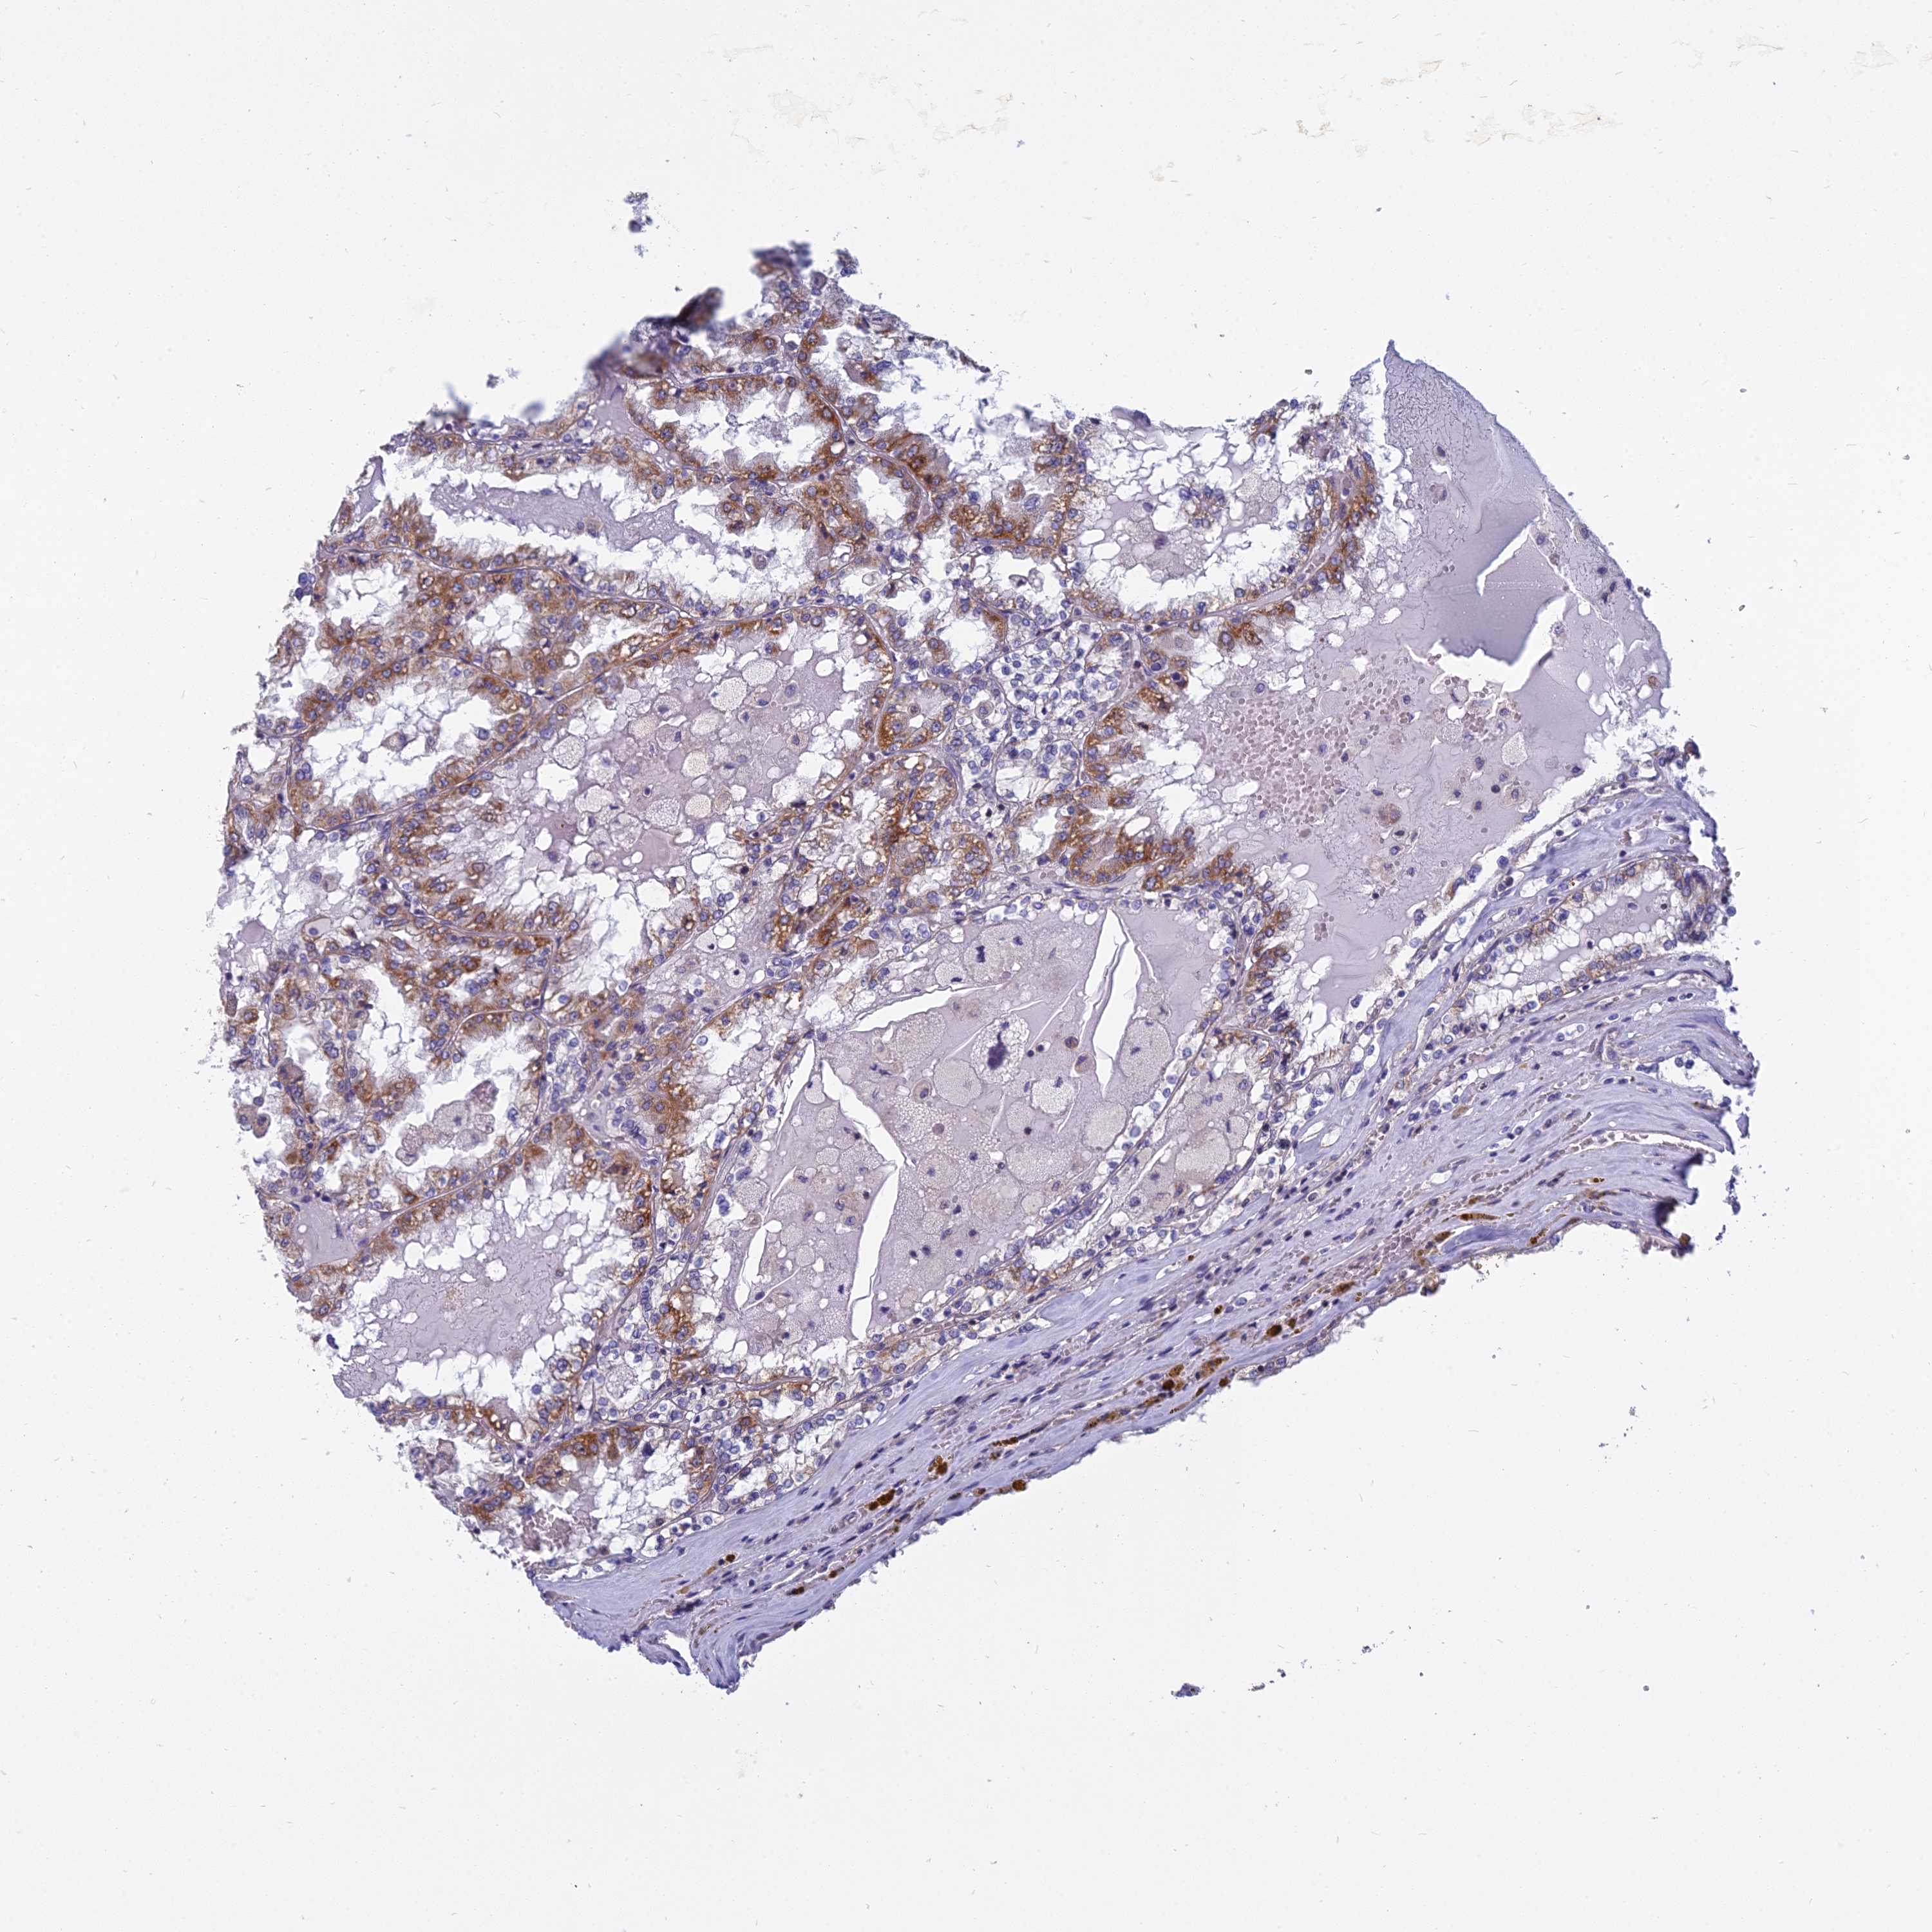

KIDNEY RENAL PAPILLARY CELL CARCINOMA (TCGA) - Interactive survival scatter ploti

The Survival Scatter plot shows the clinical status (i.e. dead or alive) for all individuals in the patient cohort, based on the same data that underlies the corresponding Kaplan-Meier plots. Patients that are alive at last time for follow-up are shown in blue and patients who have died during the study are shown in red.

The x-axis shows the expression levels (FPKM) of the investigated gene in the tumor tissue at the time of diagnosis. The y-axis shows the follow-up time after diagnosis (years). Both axes are complimented with kernel density curves demonstrating the data density over the axes. The top density plot shows the expression levels (FPKM) distribution among dead (red) and alive patients (blue). The right density plot shows the data density of the survived years of dead patients with high and low expression levels respectively, stratified using the cutoff indicated by the vertical dashed line through the Survival Scatter plot. This cutoff is automatically defined based on the FPKM cutoff that minimizes the p-score. The cutoff can be changed by dragging the vertical line or by entering a cutoff value in the square labeled "Current cut-off".

Under the Survival Scatter plot the p-score landscape (black curve; left axis) is shown together with dead median separation (red curve; right axis). Dead median separation is the difference in median mRNA expression between patients who have died with high and low expression, respectively. It is calculated as follows: median FPKM expression of dead patients with high expression - median FPKM expression of dead patients with low expression. This is intended to aid the user in visually exploring custom cutoffs and the associated p-scores and dead median separation.

Individual patient data is displayed and can be filtered by clicking on one or more of the category buttons on the top of the page. Categories describing expression level and patient information include: high, low, alive, dead, female, male and tumor stages. The scale of the x-axis can be toggled between linear and log-scale by clicking on the "x log" button. Mouse-over function shows TCGA ID, patient information and mRNA expression (FPKM) for each patient.

& Survival analysisi

Kaplan-Meier plots summarize results from analysis of correlation between mRNA expression level and patient survival. Patients were divided based on level of expression into one of the two groups "low" (under cut off) or "high" (over cut off). X-axis shows time for survival (years) and y-axis shows the probability of survival, where 1.0 corresponds to 100 percent.

COX20 is not prognostic in Kidney Renal Papillary Cell Carcinoma (TCGA)